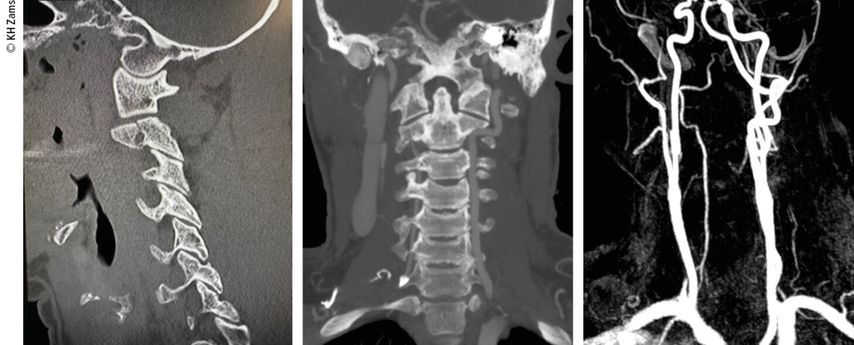

Vaskuläre Pathologien der Halswirbelsäule, insbesondere Dissektionen der A. carotis oder der A. vertebralis, sind potenziell lebensbedrohliche Zustände. Sie treten häufig infolge von stumpfen oder penetrierenden Traumata auf und sind klinisch oft schwer zu erkennen. Die frühzeitige multimodale Diagnostik und das adäquate interdisziplinäre Management sind von essenzieller Bedeutung für eine erfolgreiche Behandlung.

In der vorderen Halsregion liegt die A. carotis communis, diedem Aortenbogen (links) bzw. dem Truncus brachiocephalicus (rechts) entspringt. Sie teilt sich typischerweise auf Höhe des dritten bis vierten Halswirbels in die zwei wichtigsten Endäste für die Versorgung von Kopf und Hals. Bei dieser Gabelung befindet sich der Bulbus caroticus als Teil des sinuaortalen Systems. Etwas 2–3cm distal des Bulbus befindet sich die typische extrakranielle Lokalisation für Dissektionen. Die A. vertebralis entspringt in 90% der Fälle der Hinterwand der A. subclavia. Der Gefäßverlauf wird vom Ursprung der Arterie bis zur hinteren Schädelgrube unter anatomischen und klinischen Gesichtspunkten in vier Abschnitte unterteilt: